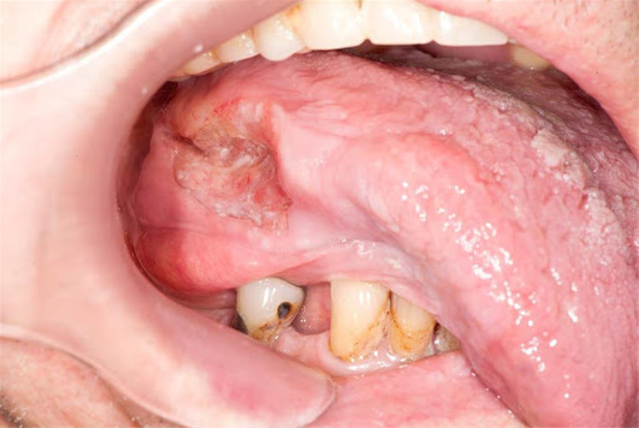

Ung thư miệng xảy ra khi các tế bào tăng sinh và phát triển bất thường trong các mô của miệng hoặc cổ họng. Các tế bào vảy là các tế bào mỏng, phẳng nằm bên trong miệng thường là nơi bắt đầu ung thư miệng. Hút thuốc và uống rượu là những yếu tố nguy cơ chính gây nên gây bệnh. Chúng ta hãy cùng tìm hiểu cụ thể hơn ung thư miệng là gì cũng như những biện pháp phòng tránh qua bài viết sau.